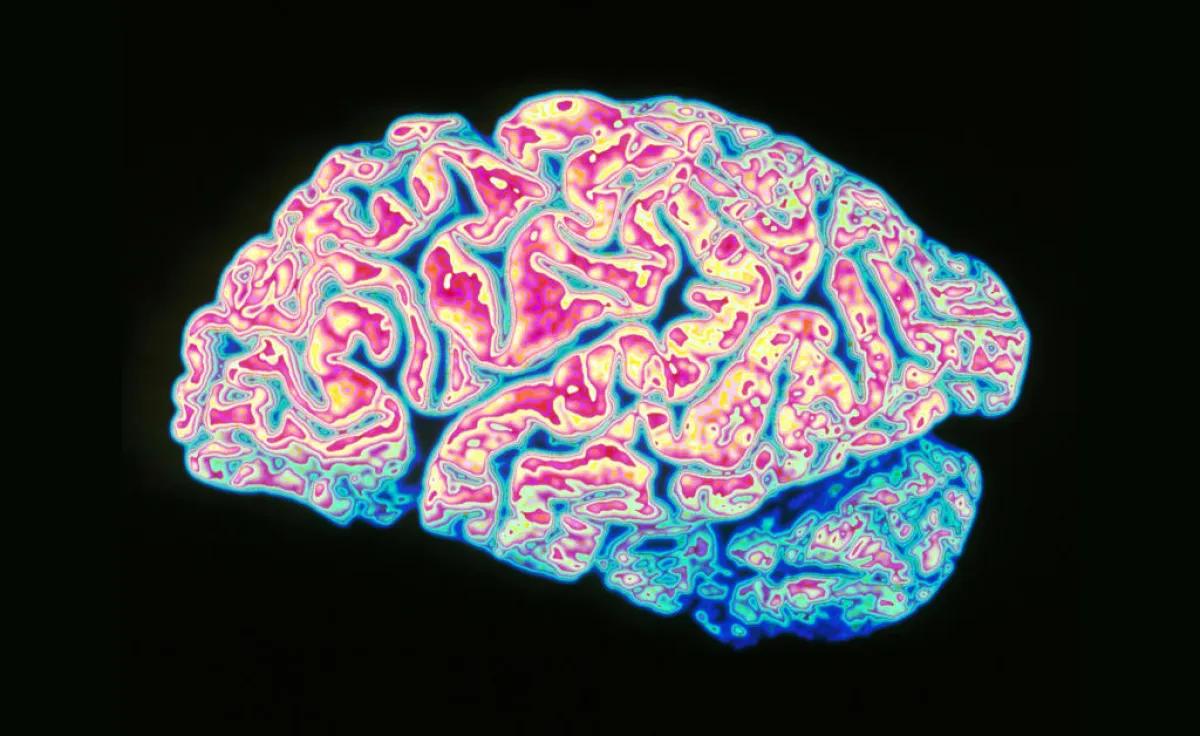

بدراسة فريدة هي الأولى من نوعها على الإطلاق، كشفت دراسة علمية جديدة أجراها عدد من العلماء في جامعة بوسطن بولاية ماساشوستس الأميركية، أن الدماغ البشري يقوم بالتخلص من مواد معينة عندما يخلد الإنسان إلى النوم، وذلك بهدف إراحة الجسد ومساعدته على أن يواصل العمل بشكل طبيعي. وأطلق العلماء على هذه المواد اسماً غير متوقع وهو فضلات الدماغ.

وذكر موقع سكاي نيوز نقلاً عن موقع ميديكال نيوز توداي، أن الدماغ البشري يقوم بإرسال العديد من الموجات الكهربائية، التي تقوم بما يشبه «عملية الغسل» للسائل الدماغي الشوكي، وذلك حتى تخلصه من مواد عديدة وصفها العلماء الأمريكيون بأنها تعادل الفضلات.

إذ اكتشف الباحثون في جامعة بوسطن، أن وظائف النوم تتعدى فكرة إعادة تنشيط الجسد، لتصل إلى إتاحة المجال أمام ما اعتبروه عملية تنظيف الدماغ.

وأشاروا إلى أن هنالك العديد من التفاعلات التي تكون على شكل موجات، تحدث في السائل الموجود بكل من الدماغ والحبل الشوكي. حيث تعمل هذه الموجات على التخلص من تراكم فضلات الأيض. وأوضحت لورا لويس، من الباحثين القائمين على الدراسة في الجامعة الأمريكية، أن العلماء في السابق، كانوا يعرفون عن وجود نشاط للموجات الكهربائية في الخلايا العصبية، إلا أن هذه الدراسة أتاحت لهم اكتشافاً فريداً لأول مرة، بأن هنالك نشاط مشابه لهذه الموجات في السائل الدماغي الشوكي.

وبيّن موقع ميديكال نيوز توداي، أن الدراسة التي من المفترض صدورها في صحيفة ساينس العلمية الشهيرة خلال الفترات القادمة، كانت قد أجريت على 13 شخصاً، تترواح أعمارهم ما بين الـ23 إلى 33 عاماً. كانوا قد خضعوا إلى عدد من الفحوصات للدماغ خلال فترة نومهم، وذلك عبر ارتدائهم أجهزة تخطيط كهربائية خاصة بالدماغ. وعليه فقد كشفت النتائج أن سائل الدماغ الشوكي، يعمل على التفاعل بشكل منسجم مع موجات الدماغ، وذلك بهدف التخلص من فضلاته، والتي أوضح الباحثون أنها عبارة عن عناصر مختلفة لا حاجة إليها، مثل بعض البروتينات السامة التي تقوم بعمل حاجز يعيق تدفق المعلومات بين الخلايا العصبية.